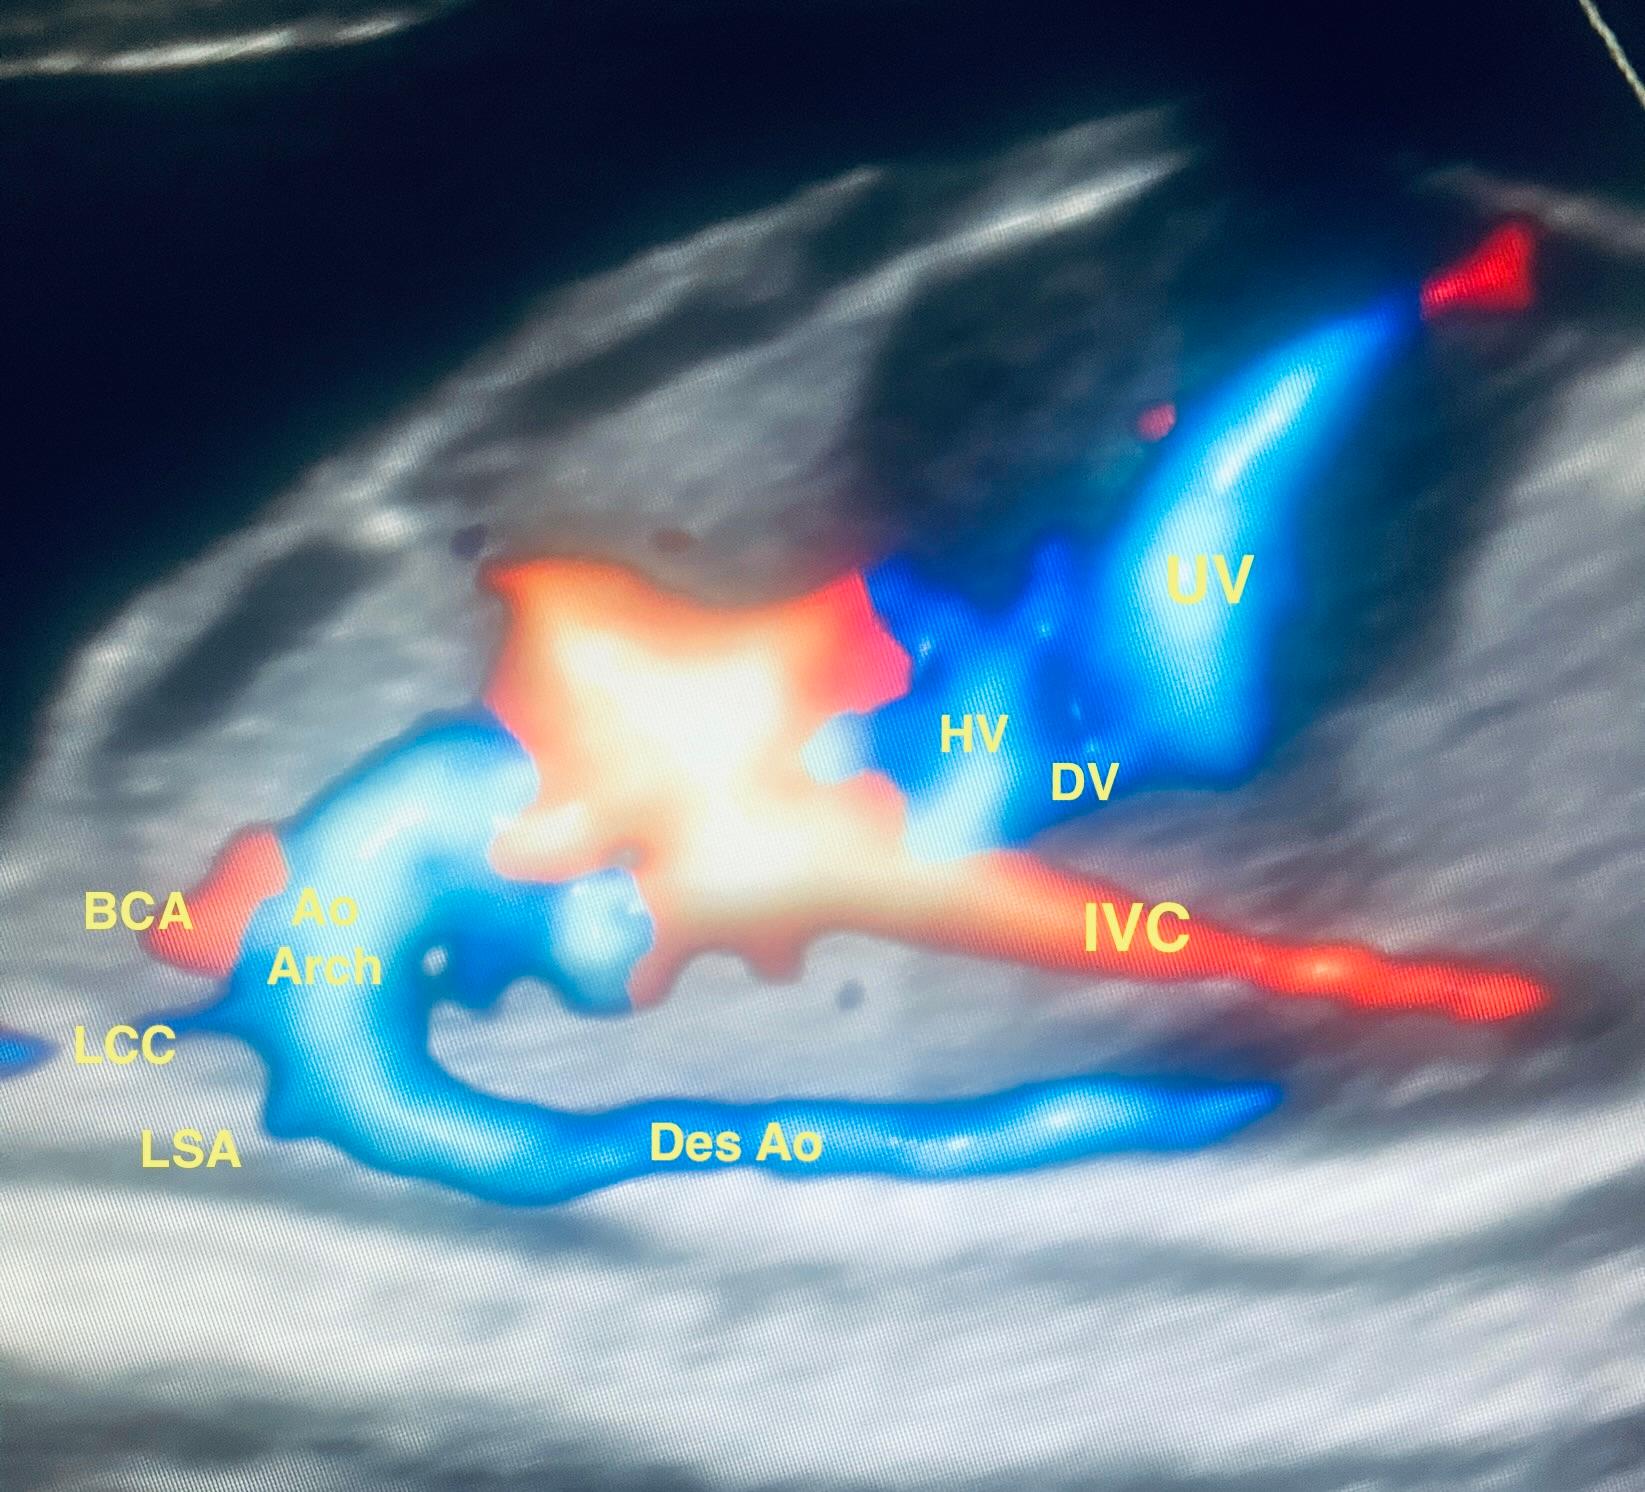

Decoding the Four-Chamber Heart View: Mastering Ultrasound Insights

Master the Four-Chamber View:Enhance your skills in fetal heart imaging. Learn to detect congenital heart anomalies and optimize your ultrasound technique with standardized diagnostic criteria. Perfect for professionals seeking sharper interpretation and scanning precision.

Master fetal heart interpretation using the four-chamber view.

Identify congenital heart defects with standard diagnostic criteria.

Optimize scanning techniques for accurate prenatal detection.